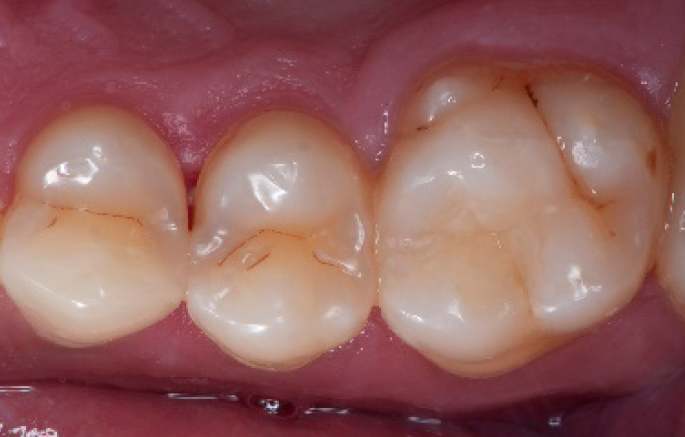

After

Final situation 2 weeks after the filling. Great comfort and no sensitivity at all were reported by the patient.

Step 14:

2 weeks control